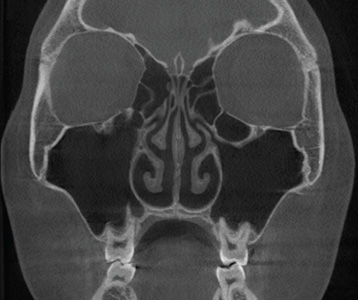

재수술 전

재수술 후